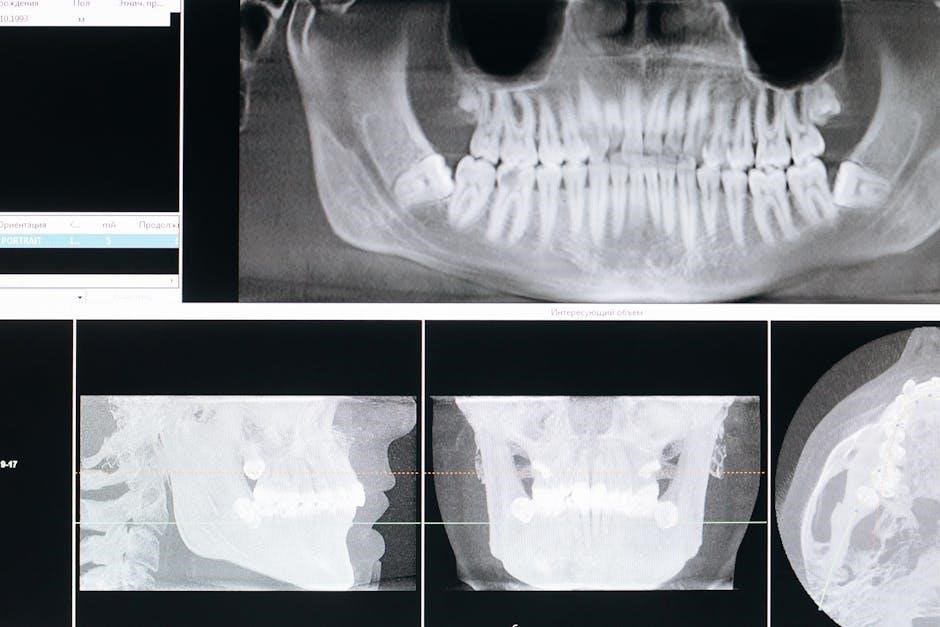

5.1 Pre-Surgical Evaluation and Planning

Pre-surgical evaluation involves assessing bone density and volume using CBCT scans and radiographs. Treatment planning includes identifying defect locations and determining the need for bone grafts or membranes. Dental codes like D7953 are considered for billing purposes. Patient-specific factors, such as medical history and implant placement goals, are evaluated to ensure personalized care. Accurate planning is crucial for successful GBR outcomes and minimizing complications during surgery.